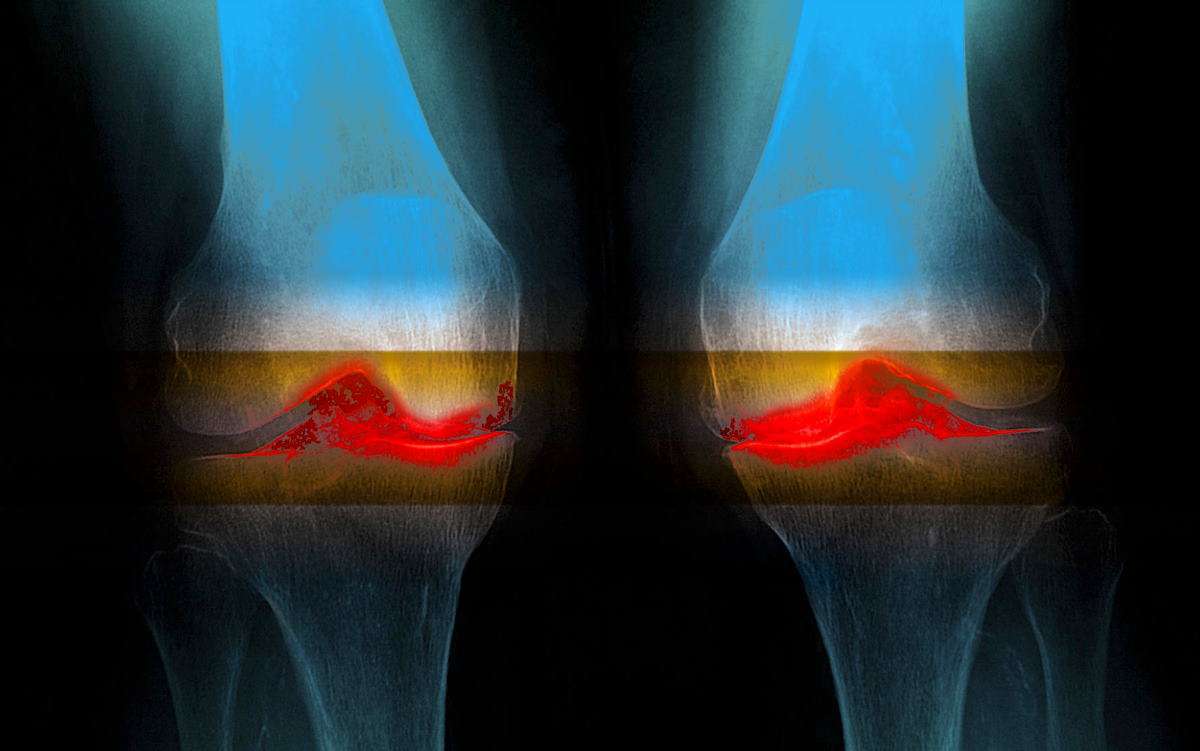

Медицинские состояния: Септический артрит коленного сустава